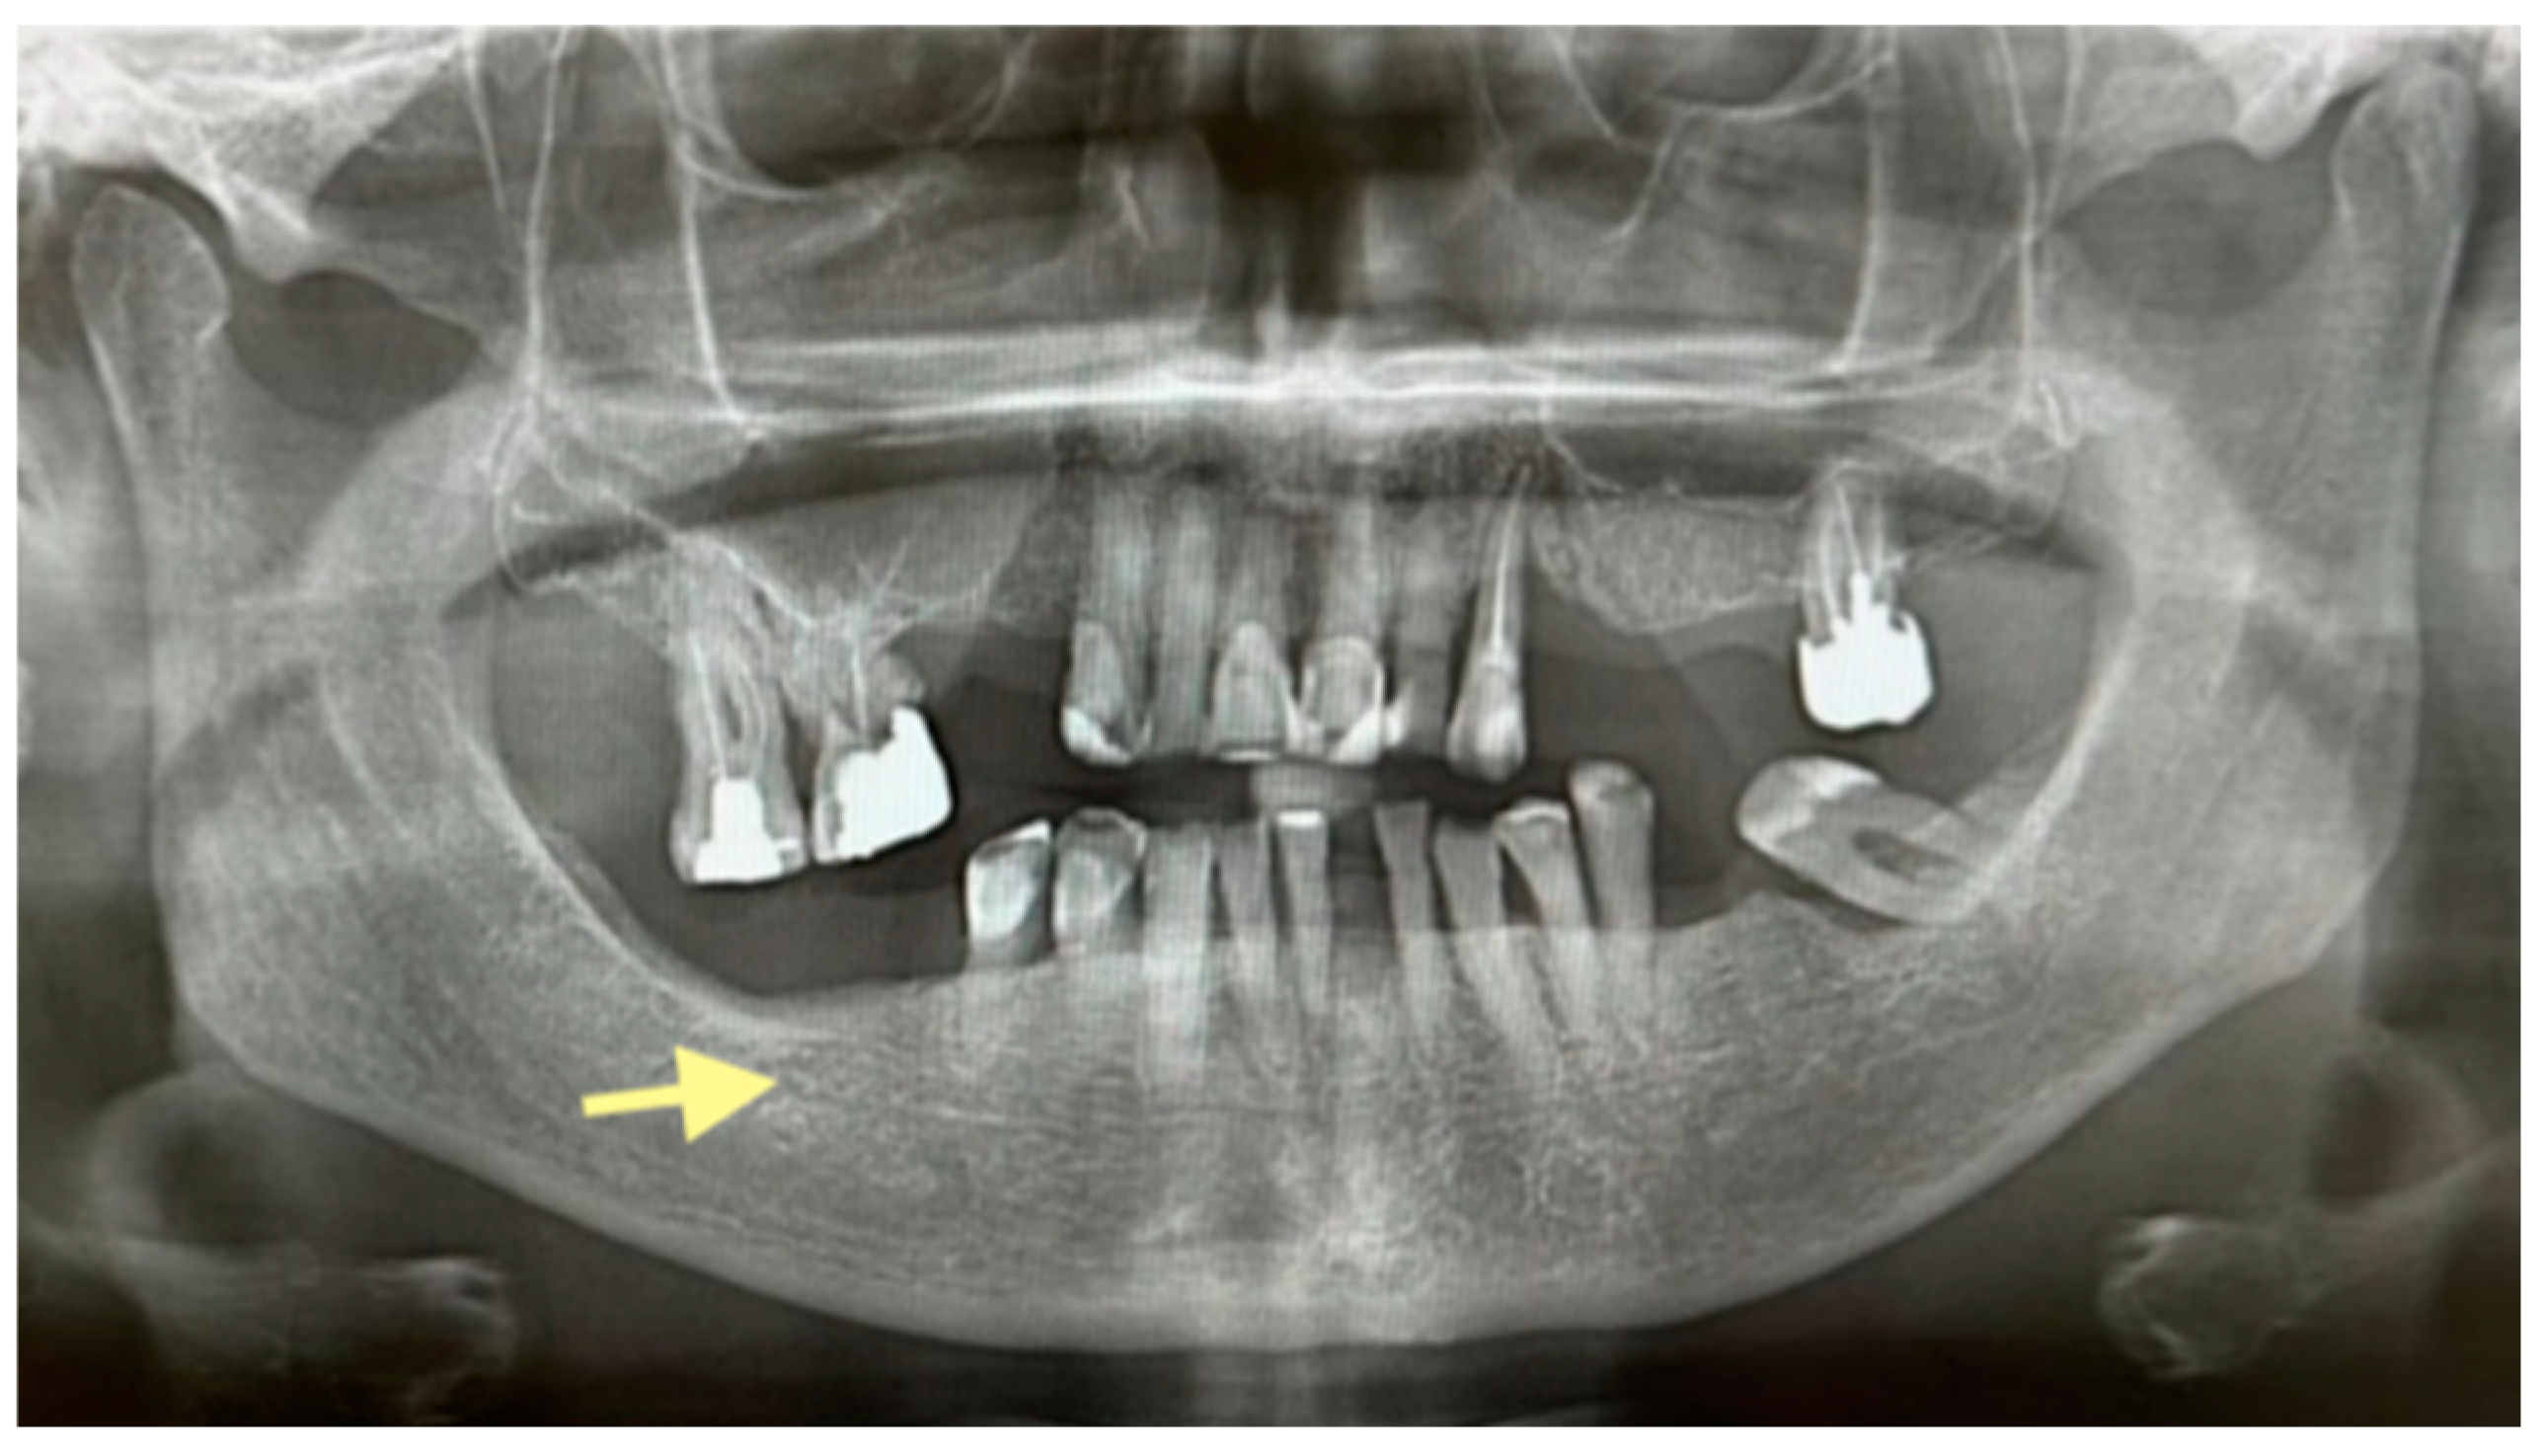

Figure 4.

OPG (orthopantomogram) before surgery (12 January 2024). In the fourth quadrant, we do not see any changes, which are typical in the initial stages of osteonecrosis.